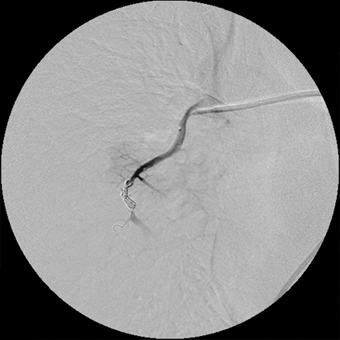

血管撮影にて

異常血管を確認

金属コイルにて

異常血管を塞栓し消失